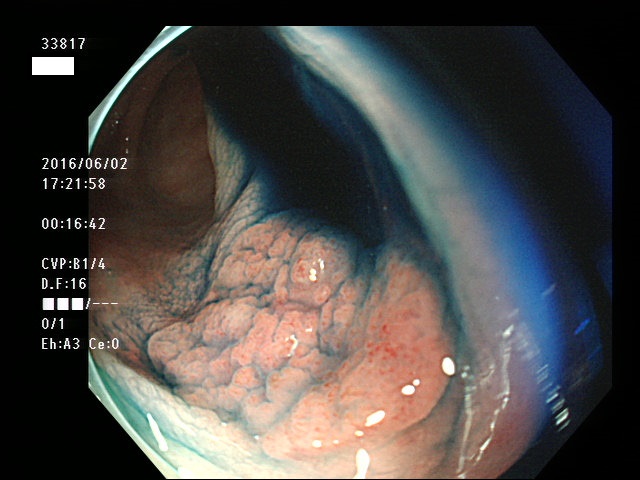

上記100名より抽出した平坦・陥凹型腺腫(=癌化の危険が高いが見落としやすい病変)の内視鏡写真